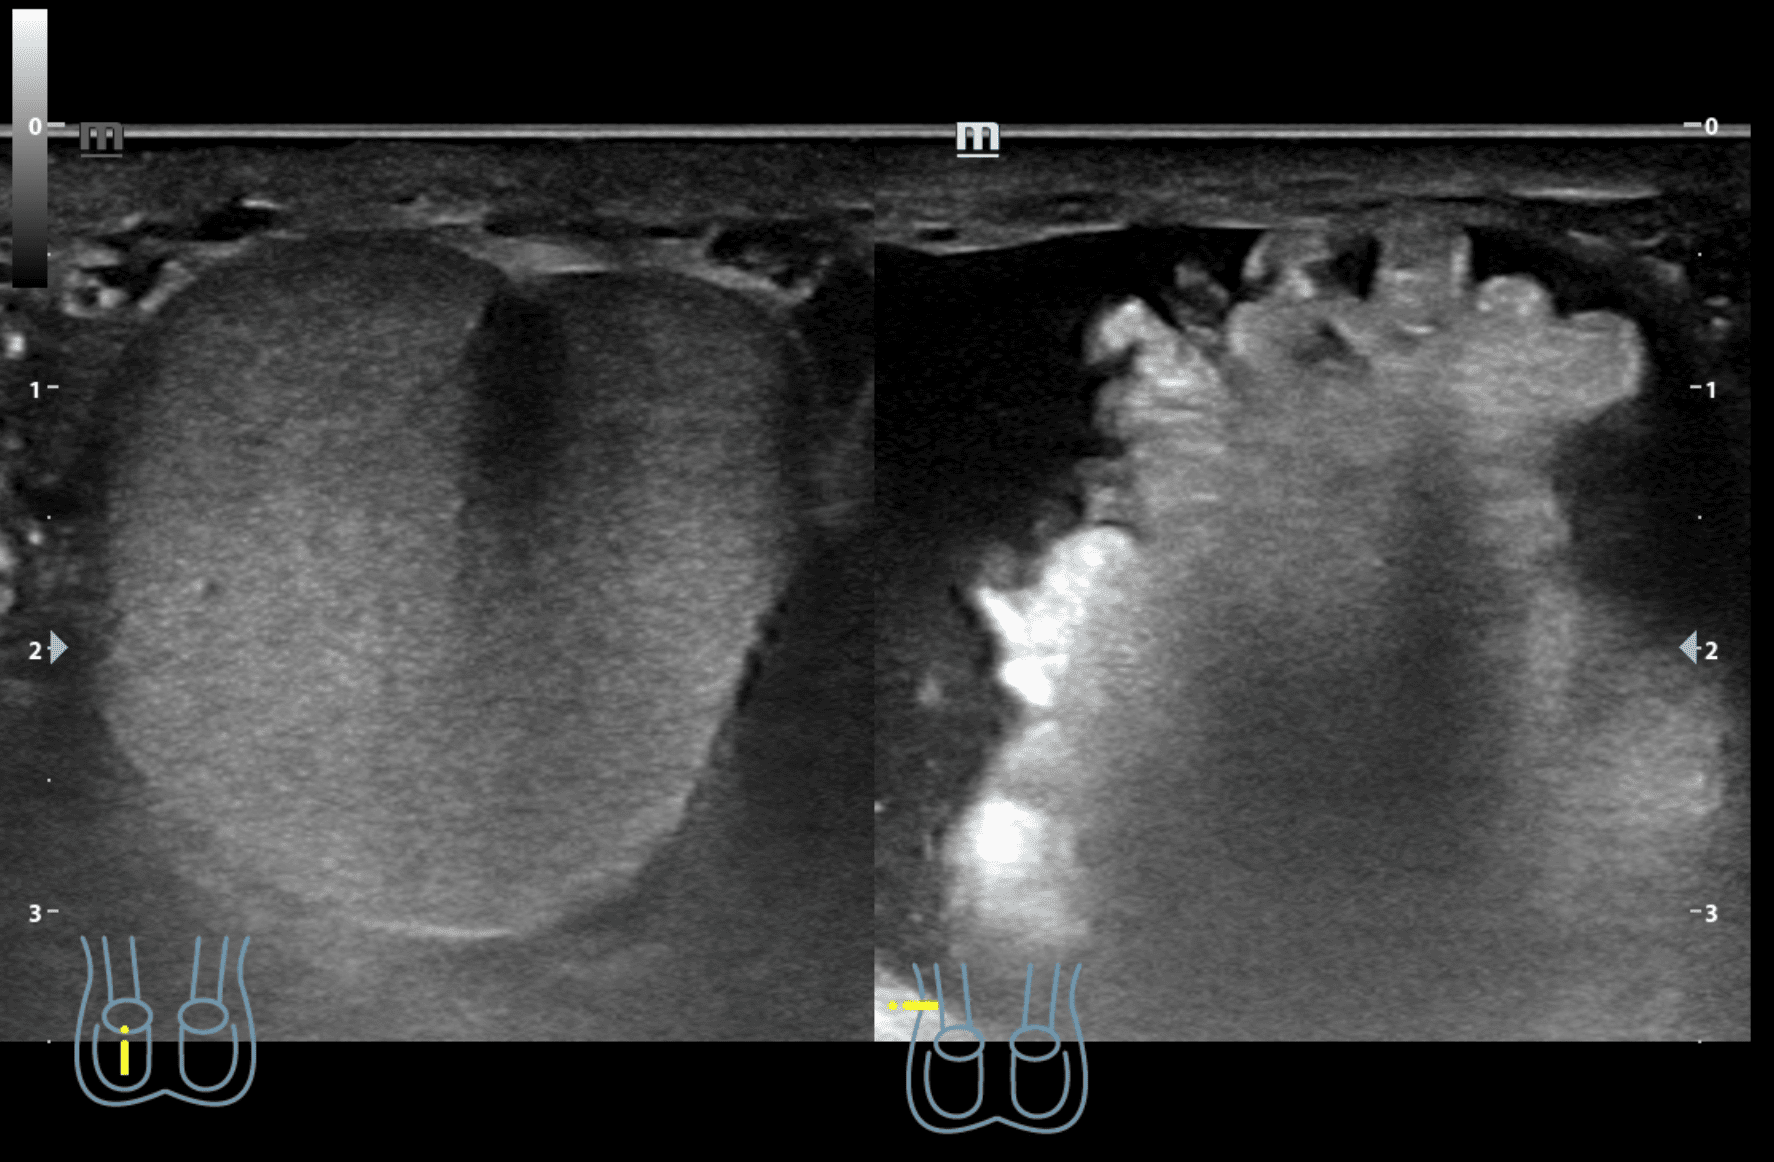

A nivel de escroto derecho, se observa imagen heterogénea con contenido intestinal compatible con hernia inguino-escrotal derecha. Testículos de aspecto normal.

Hernia inguino-escrotal derecha reductible dolorosa, no complicada.